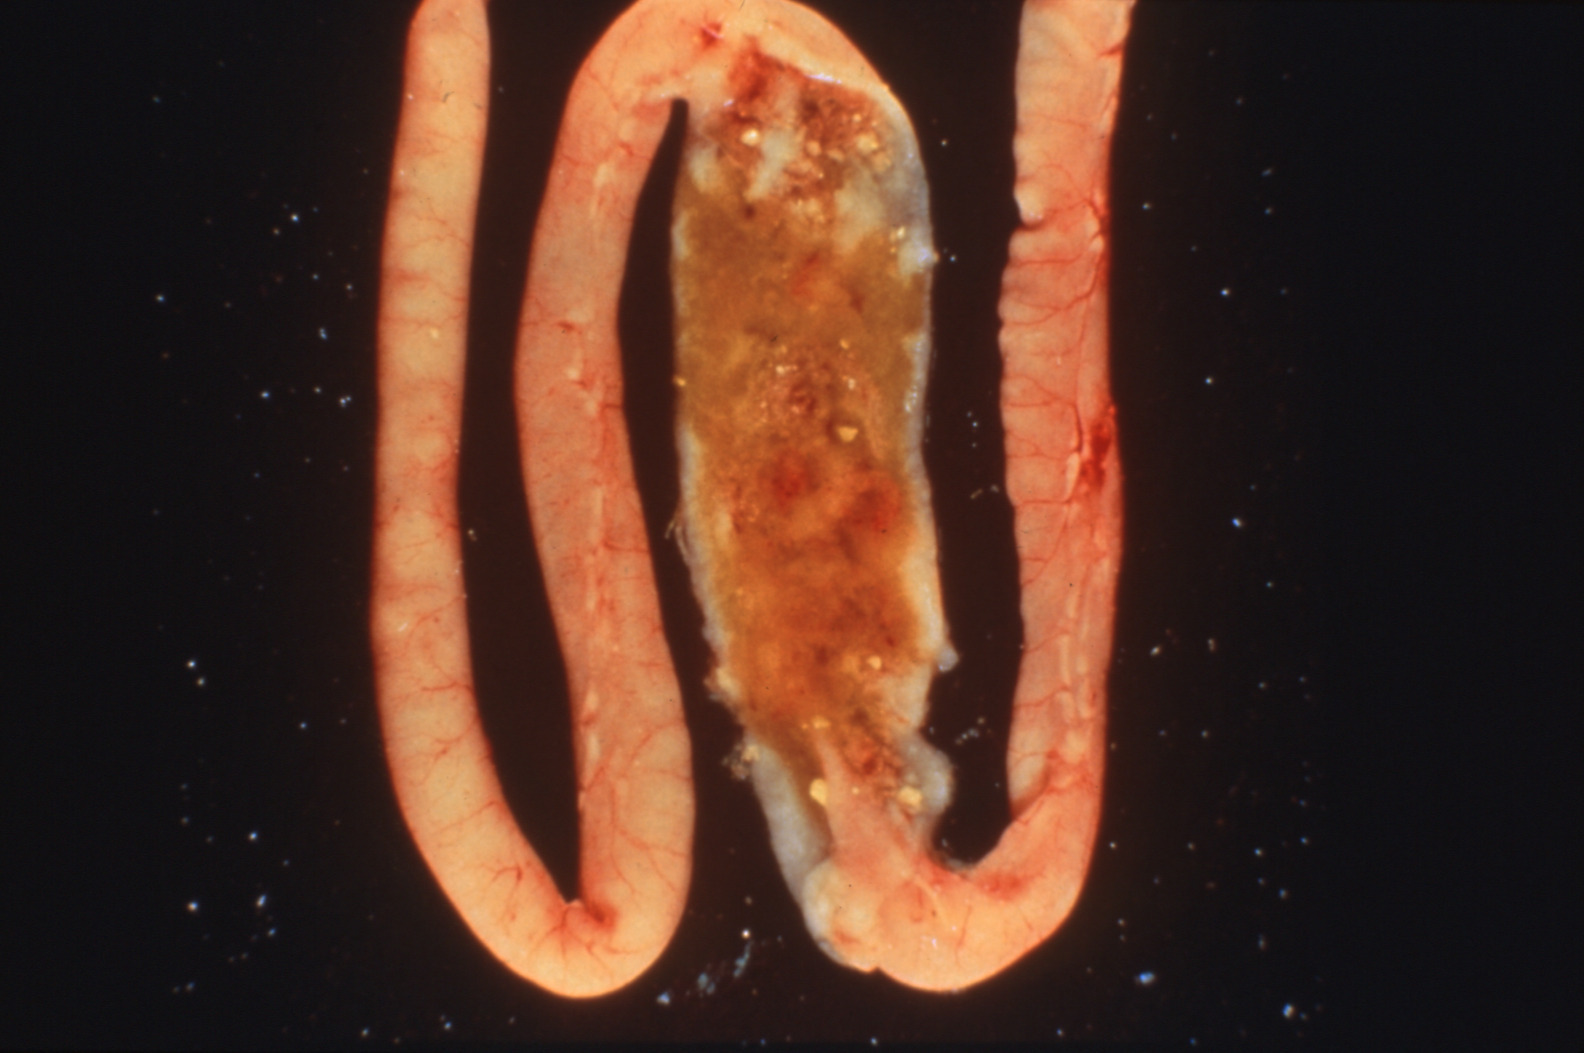

Coccidiosis in chickens and turkeys (slide study set no. 7)

Avian coccidiosis Avian medicine Chickens--Diseases Turkeys--Diseases